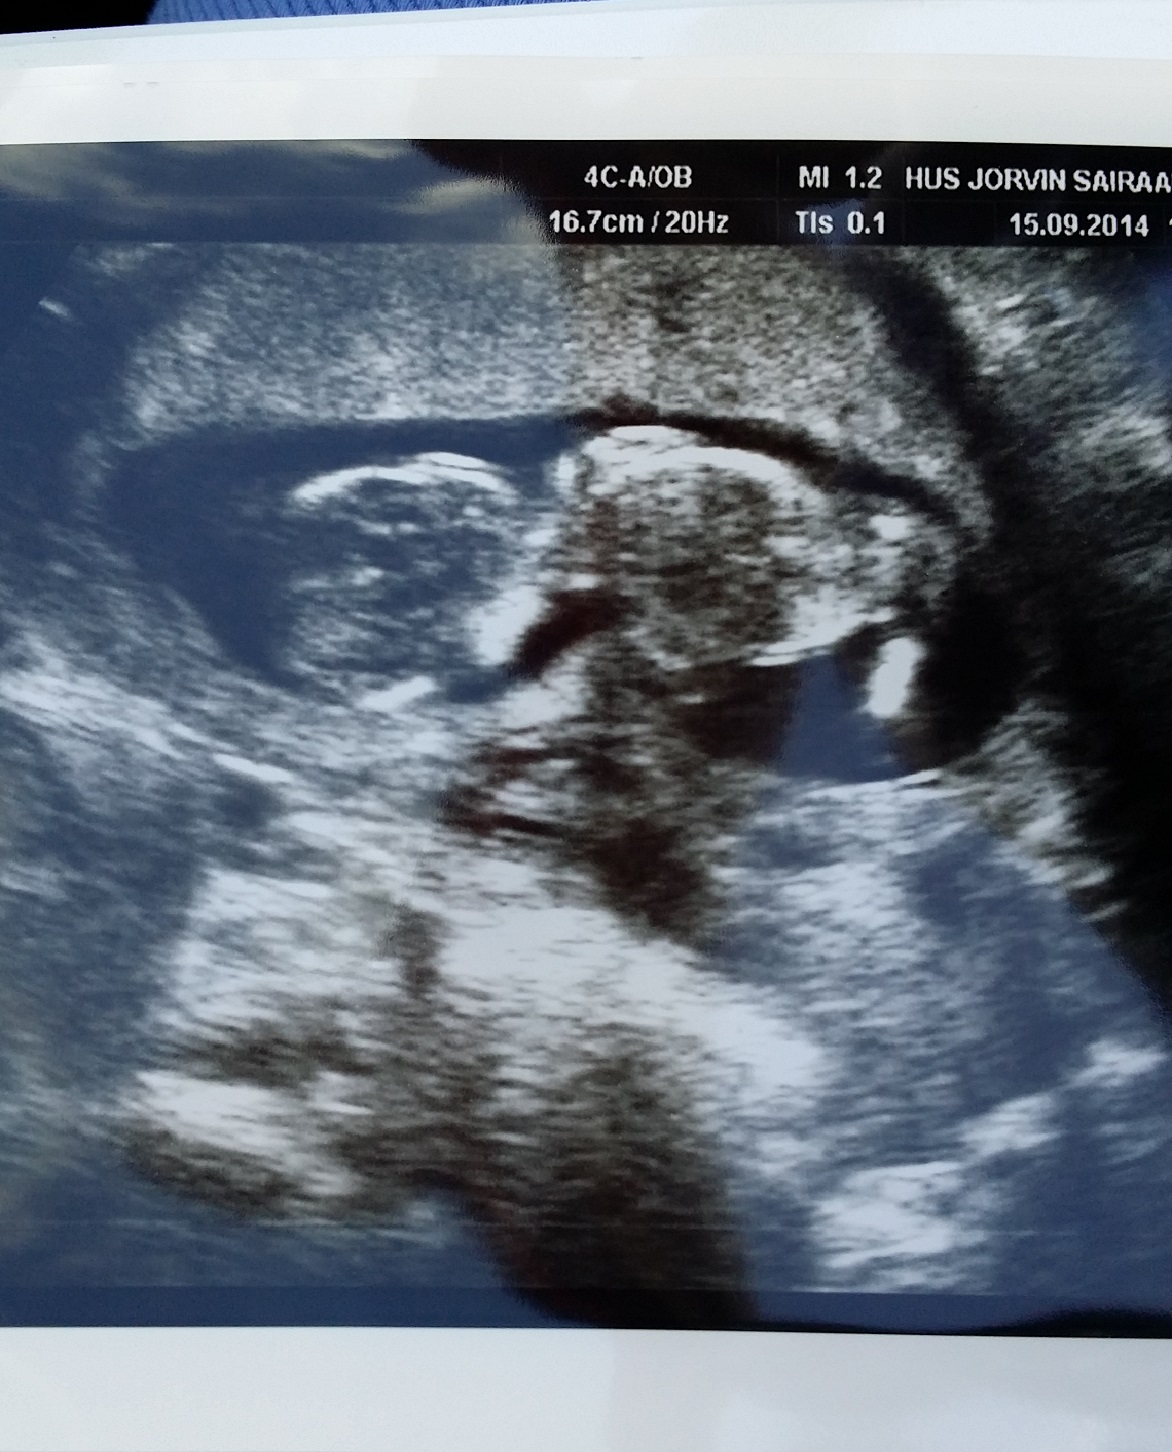

Tänään siis päivystyksessä ultrattu ilman sykettä ja huomiselle sain cytotecit lääkkeellistä tyhjennystä varten, kun keskeytynyt keskenmeno oli diagnoosi. Saikkua seuraavat 3 päivää ja piti pyytää uusi todistus, kun lääkäri niin avuliaasti kirjoitti ihan selkokielisenä syynkin. Ihan kuin koko toimistolle nyt olisi tarve kertoa noin tyhjentävästi tämä asia, kun itse raskauskin oli vielä salaisuus.